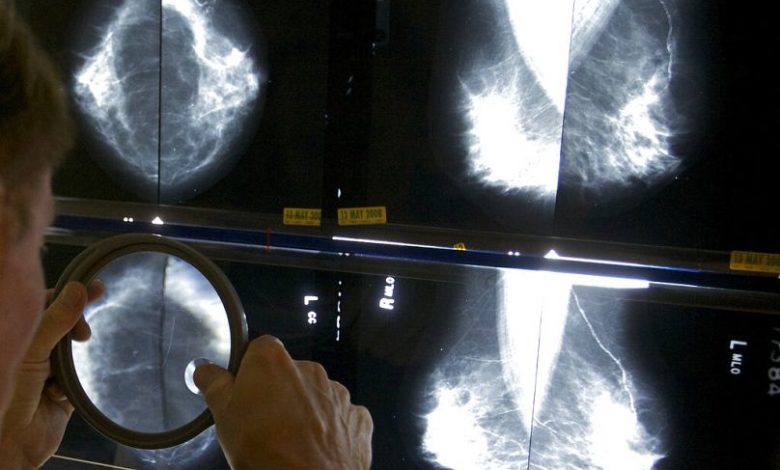

متاستاز به دیگر نقاط بدن یکی از مشکلات عمده سرطان پستان به شمار میرودعکس: آسوشیتد پرس